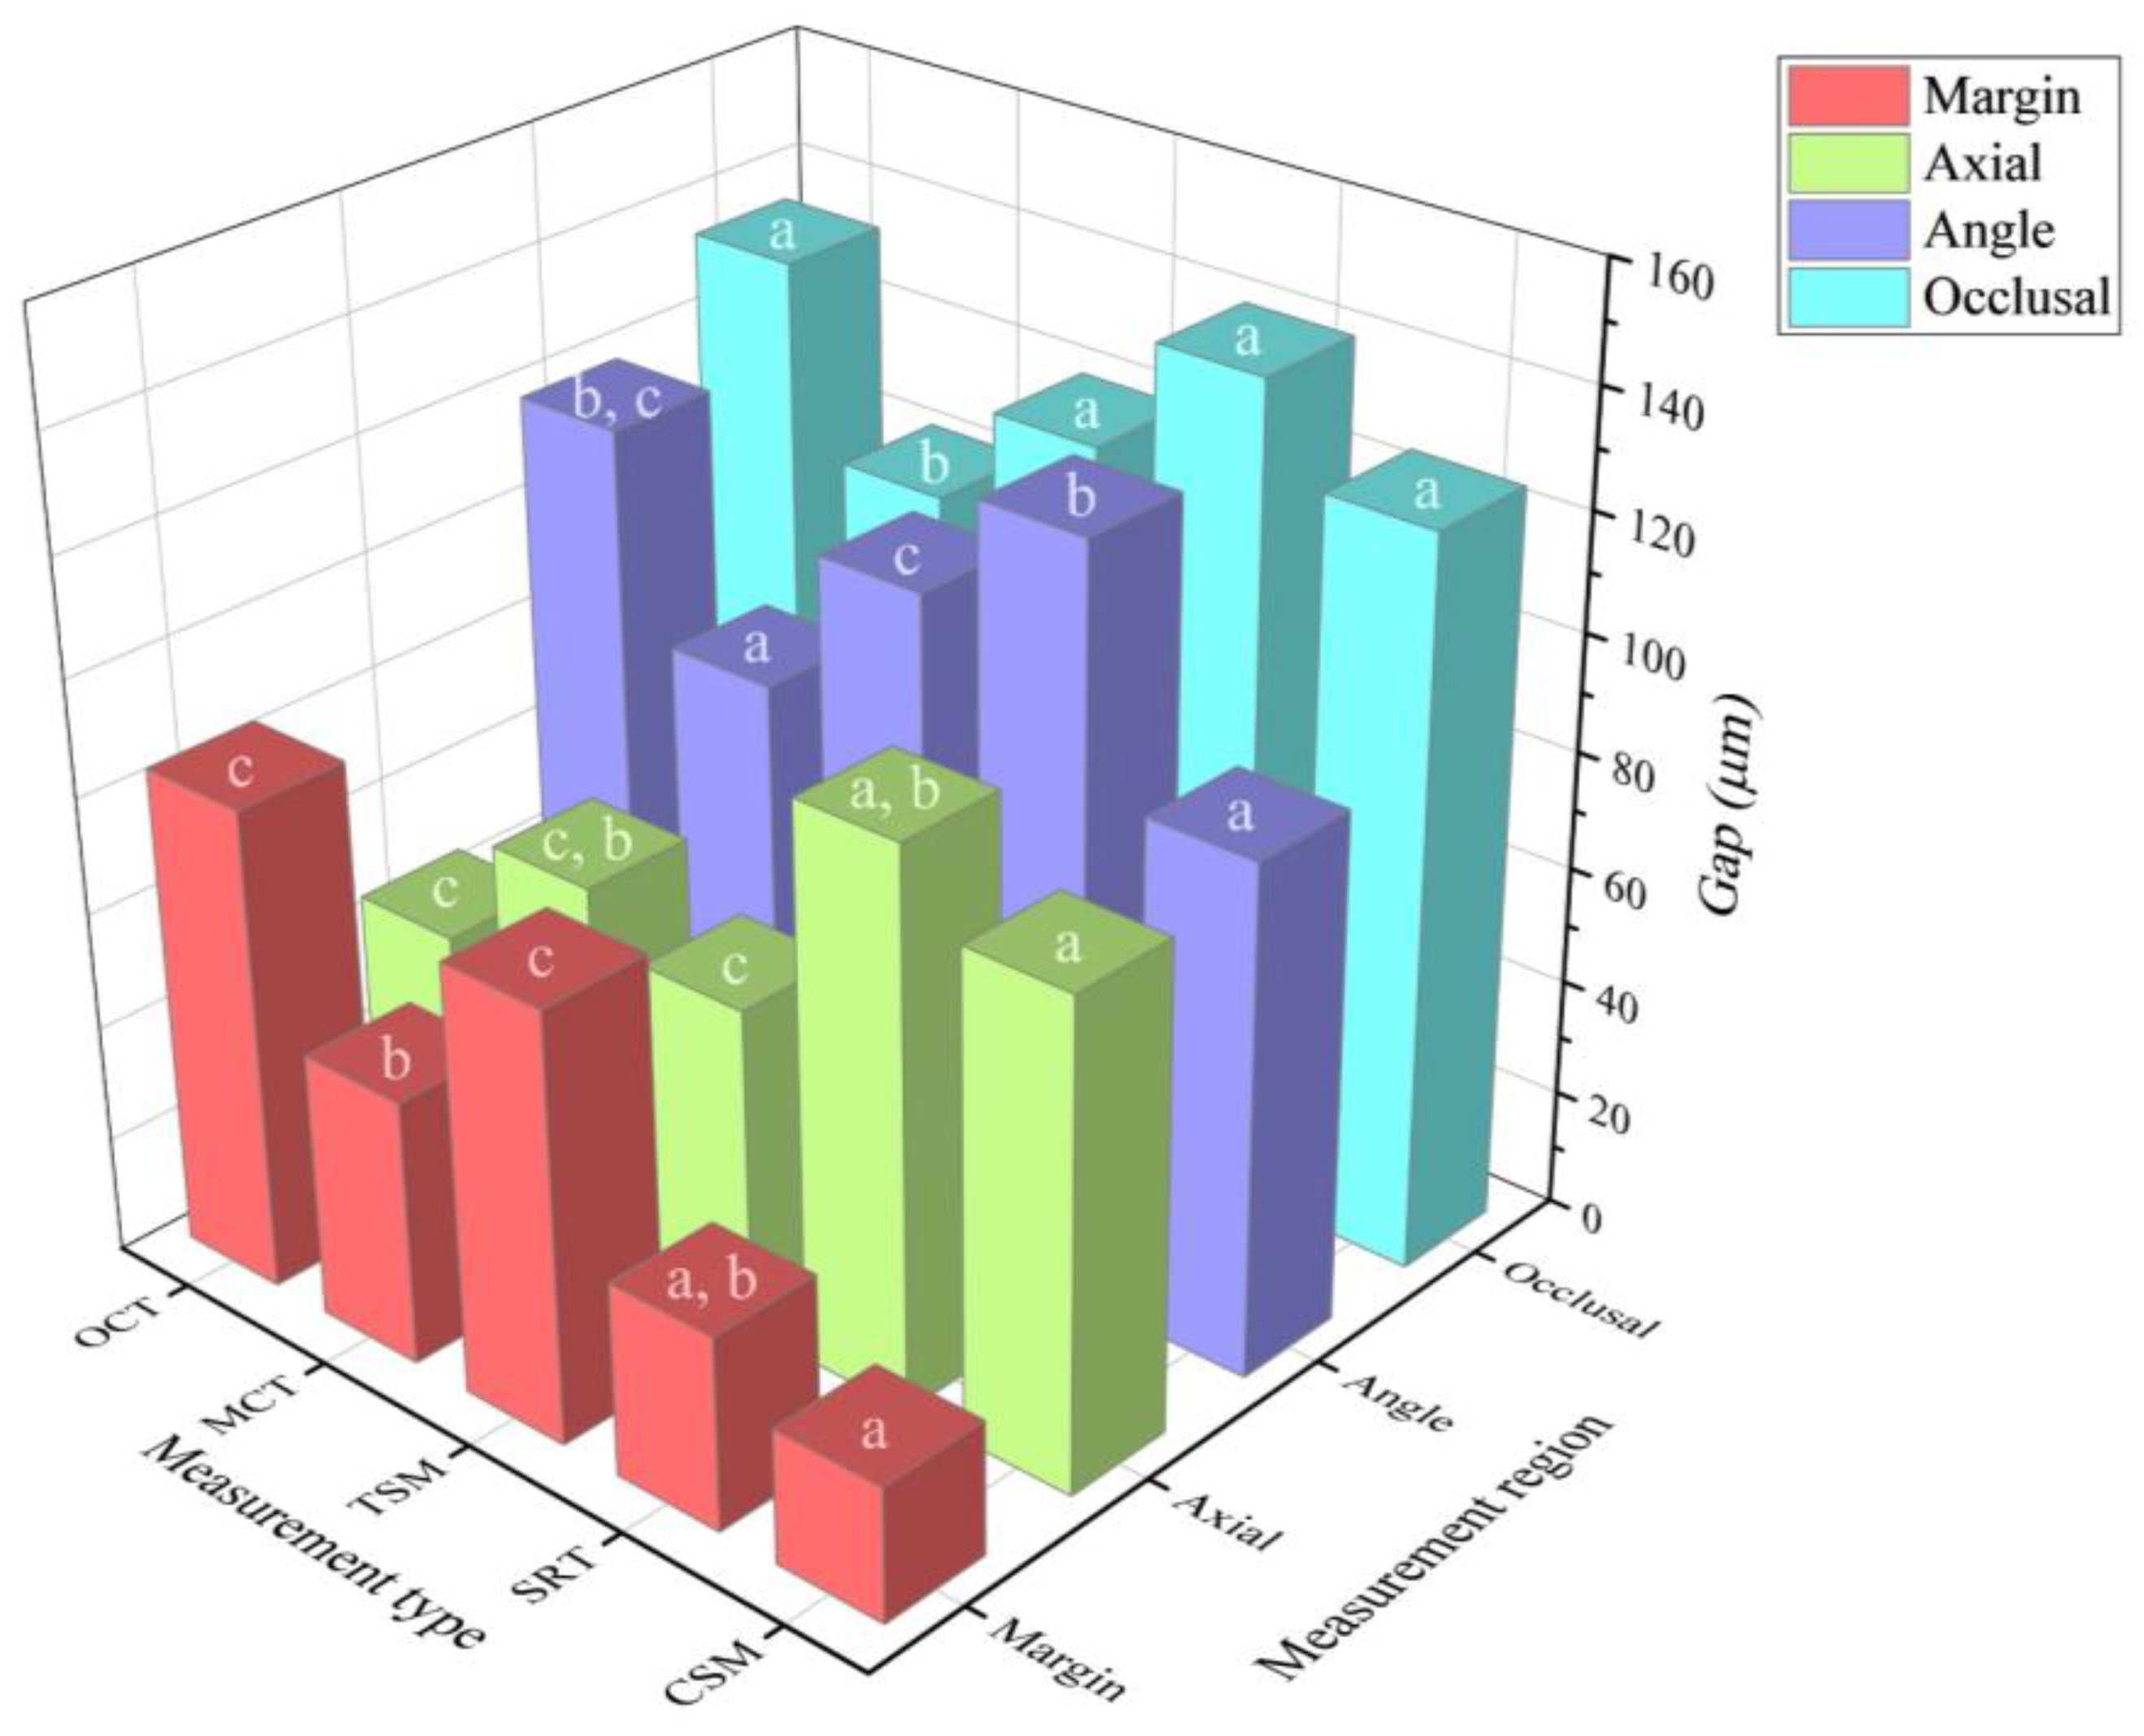

3. Results

| Test method | Margin | Axial | Angle | Occlusal |

|---|---|---|---|---|

| CSM | 23.2 ± 5.3 a | 83.7 ± 19.8 a | 87.9 ± 17.2 a | 125.4 ± 13.7 a |

| SRT | 33.5 ± 12.1 a,b | 95.9 ± 52.9 a,b | 128.6 ± 17.3 b | 140.5 ± 33.3 a |

| TSM | 74.1 ± 26.1 c | 56.3 ± 30.1 c | 110.1 ± 13.9 c | 120.3 ± 20.9 a |

| MCT | 45.9 ± 25.9 b | 65.3 ± 47.7 c,b | 84.3 ± 20.2 a | 102.6 ± 12.8 b |

| OCT | 83.4 ± 22.1 c | 44.8 ± 14.5 c | 118.2 ± 22.2 b,c | 134 ± 18.9 a |